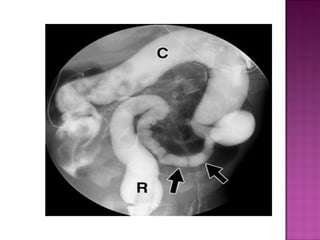

 Contrast studies-

dilated ascending & transverse colon

small descending colon

rectum normal

 Abnormal courseof duodenum that fail to cross midline has spiral appearance .

 Contrast studies- dilatedascending & transverse colon small descending colon rectum normal